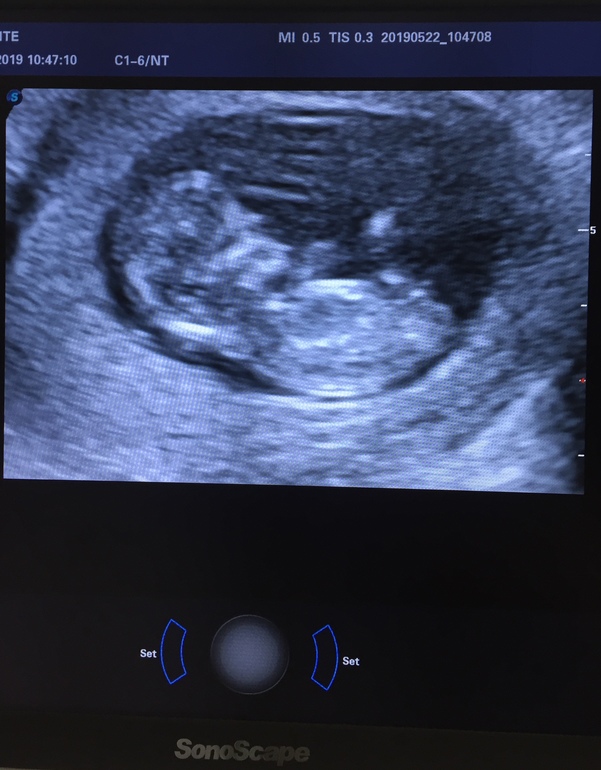

Вопросы про УЗИ, обследования и анализы: что, где, как, когда?Ну вот прошла 1 скрининг, по м срок 11+1 переживала что рано записалась и могут что то не увидеть, но рассмотрели все, врач был молчун из молчунов ничего мне не прокомментировал единственное что тонус есть якобы, и низкая плацента. А вот и сами результаты, что можете сказать девочки? Пол наверно вообще вообще рано но вдруг кто то что то заметит)

Поздравляю!!! Всё отлично! Мне это очень скоро предстоит пройти, волнуюсь страшно! Качество фото не очень, но похоже, что девочка.